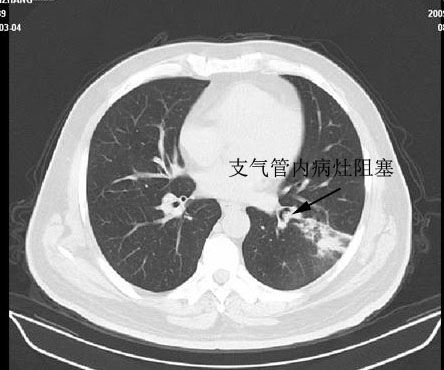

下图箭头所指为阻塞后充满粘液的扩张支气管1

该病例提示我们熟悉胸部断面解剖、特别是支气管断面解剖对诊断肺内病变的重要性